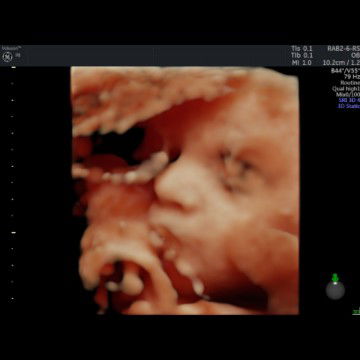

Ibu hamil

hpl April

32week..